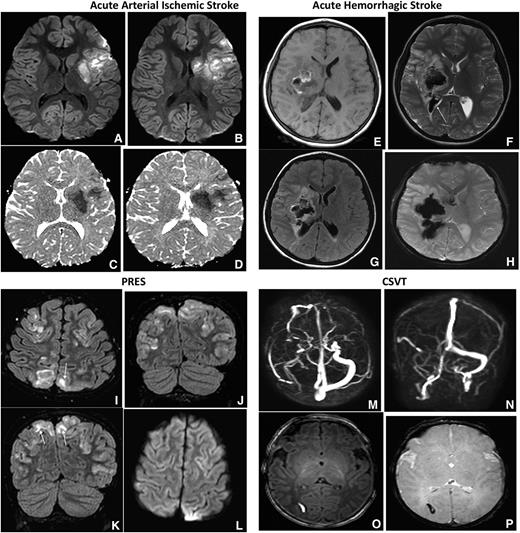

CSVT: is a less common neurologic complication in SCD when compared with ischemic strokes. Despite the low frequency, detecting the presence of CSVT is important because its presence may alter the treatment strategy. Children and adults with SCD and CSVT can present with symptoms that mimic a stroke, such as seizures, coma, cranial nerve palsies, headaches, nausea, and vomiting.33,34 An evaluation with a MRV is the preferred initial imaging study because the imaging sequence only adds a maximum of 7 minutes to the initial MRI to detect an ischemic or hemorrhagic cerebral infarct. In case 1, the MRI and MRV obtained initially excluded the possibility of CSVT, whereas in case 2, CSVT was ruled out with a subsequent MRV. The optimal duration of anticoagulation in patients with SCD presenting with focal neurologic deficit attributable to CSVT is unknown, though recent guidelines recommend 3 to 6 months with periodic reassessment of the thrombus. We recommend following approved guidelines for both acute and chronic management of CSVT, including anticoagulation.35 Figure 2A-P shows MRI findings in the differential diagnosis of patients with SCD presenting with focal neurologic deficit.

Acute arterial ischemic and hemorrhagic stroke, PRES and CSVT. Axial DWI and ADC (shown in A-B and C-D in each of the 4 sets of images, respectively) MRIs of the brain demonstrate increased DWI signal with corresponding decreased ADC signal, consistent with restricted diffusion along the left MCA territory most consistent with acute arterial ischemic stroke. Axial T1-weighted MRI (E), axial T2-weighted MRI (F), axial FLAIR (G), and axial GRE (H) images in patients with SCA demonstrate ill- defined mixed intensity focus within the right basal ganglia region with surrounding vasogenic edema. The lesion demonstrates T1 hyperintensity with hypointensity on axial T2 and GRE consistent with hemorrhage. Also seen is intraventricular extension of blood (F, arrow). GRE MR sequences are most sensitive for the detection of intracranial hemorrhage and may demonstrate more diffuse signal loss than the actual lesion, also known as blooming, as seen in this case. Axial FLAIR (I) and coronal FLAIR images MR (J-K) of the brain demonstrates bilateral near symmetric hyperintense signal involving the parieto-occipital lobes with superior frontal involvement, in a distribution and pattern most consistent with PRES. There is both subcortical (I, K arrows) and cortical involvement. Axial DWI (L) demonstrates no corresponding increased signal to suggest for restricted diffusion. Transverse (M) and coronal (N), maximum intensity projection images from a phase contrast MRV. There is no signal within the right transverse sinus due to thrombosis. Axial T1-weighted MRI (O) demonstrates a small well-defined hyperintense focus within the right occipital white matter with hypointensity on axial GRE (P), consistent with hemorrhagic venous infarction secondary to thrombosis.